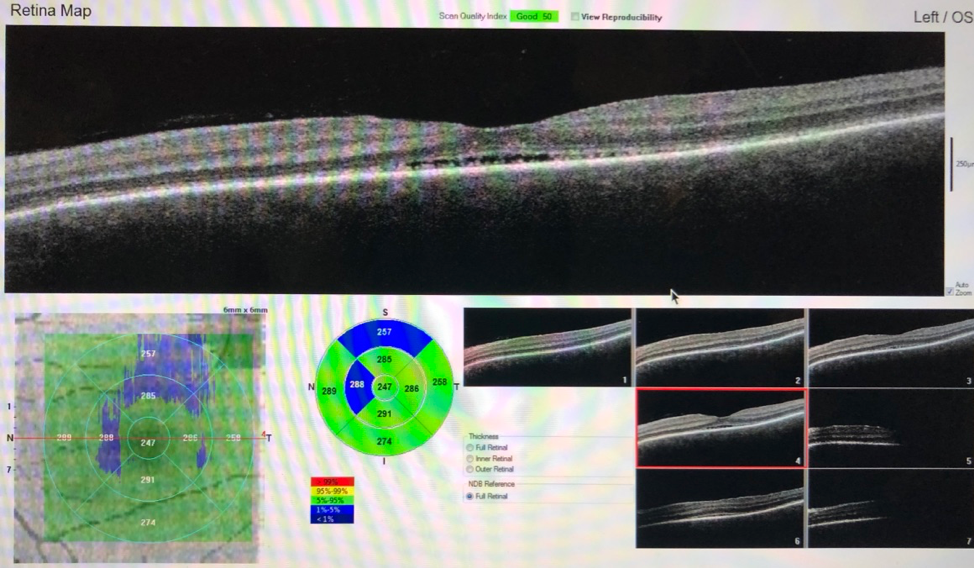

Ocular coherence tomography (OCT)—a noninvasive imaging test that uses low-coherence light to produce high-resolution cross-sectional images of the retina—demonstrated significant bilateral serous fluid with neurosensory retinal detachments of the maculae (Figure 1).

Figure 1. OCT at presentation demonstrated bilateral serous neurosensory retinal detachments of the maculae.

Figure 3. OCT demonstrated significant improvement of bilateral serous neurosensory retinal detachments 2 weeks after treatment with high-dose corticosteroids.